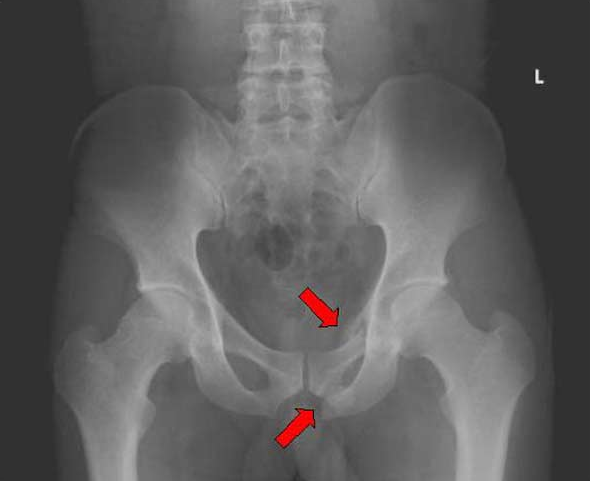

【検査】骨盤単純レントゲン…何に着目するか

大前提として正しく正面から撮られているか確認する→脊椎の最も後方で中央に位置する棘突起と左右の椎弓根との距離に左右差がなければ正面からきちんと撮られていると考えることが出来る。

問題なければ以下の9項目をチェック。

(primary-care trauma life support より引用)

1、左右対称性

2、腸骨翼の大きさ・高さ

3、恥骨結合の離開(2.5cm以上で有意)

4、臼蓋骨折

5、閉鎖孔の左右差

6、恥骨・坐骨の骨折

7、第5腰椎横突起骨折(腸腰靭帯断裂を示唆)

8、仙腸関節の離開(4mm以上で有意)

9、仙骨骨折

骨盤骨折のレントゲン例

【恥骨骨折、坐骨骨折】

画像参照:藤元メディカルシステム - 先端医療講座 - 一般撮影(レントゲン)2